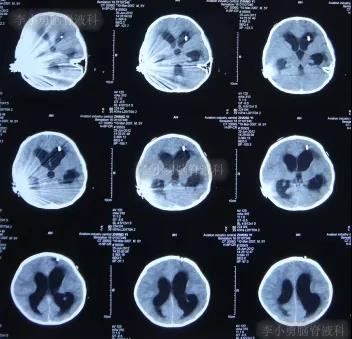

一到第3家医院,就开展了急诊气管插管和之后呼吸机辅助呼吸的抢救。住院次日,即2012年5月17日,脑CT检查并未发现明显异常(图-3)。

图-3:2012年5月17日耳蜗植入术后状态脑CT

住院3天根据腰椎穿刺脑脊液化验结果,确诊为肺炎链球菌脑膜炎,之后针对此细菌性脑膜炎的给以抗生素调整性治疗。